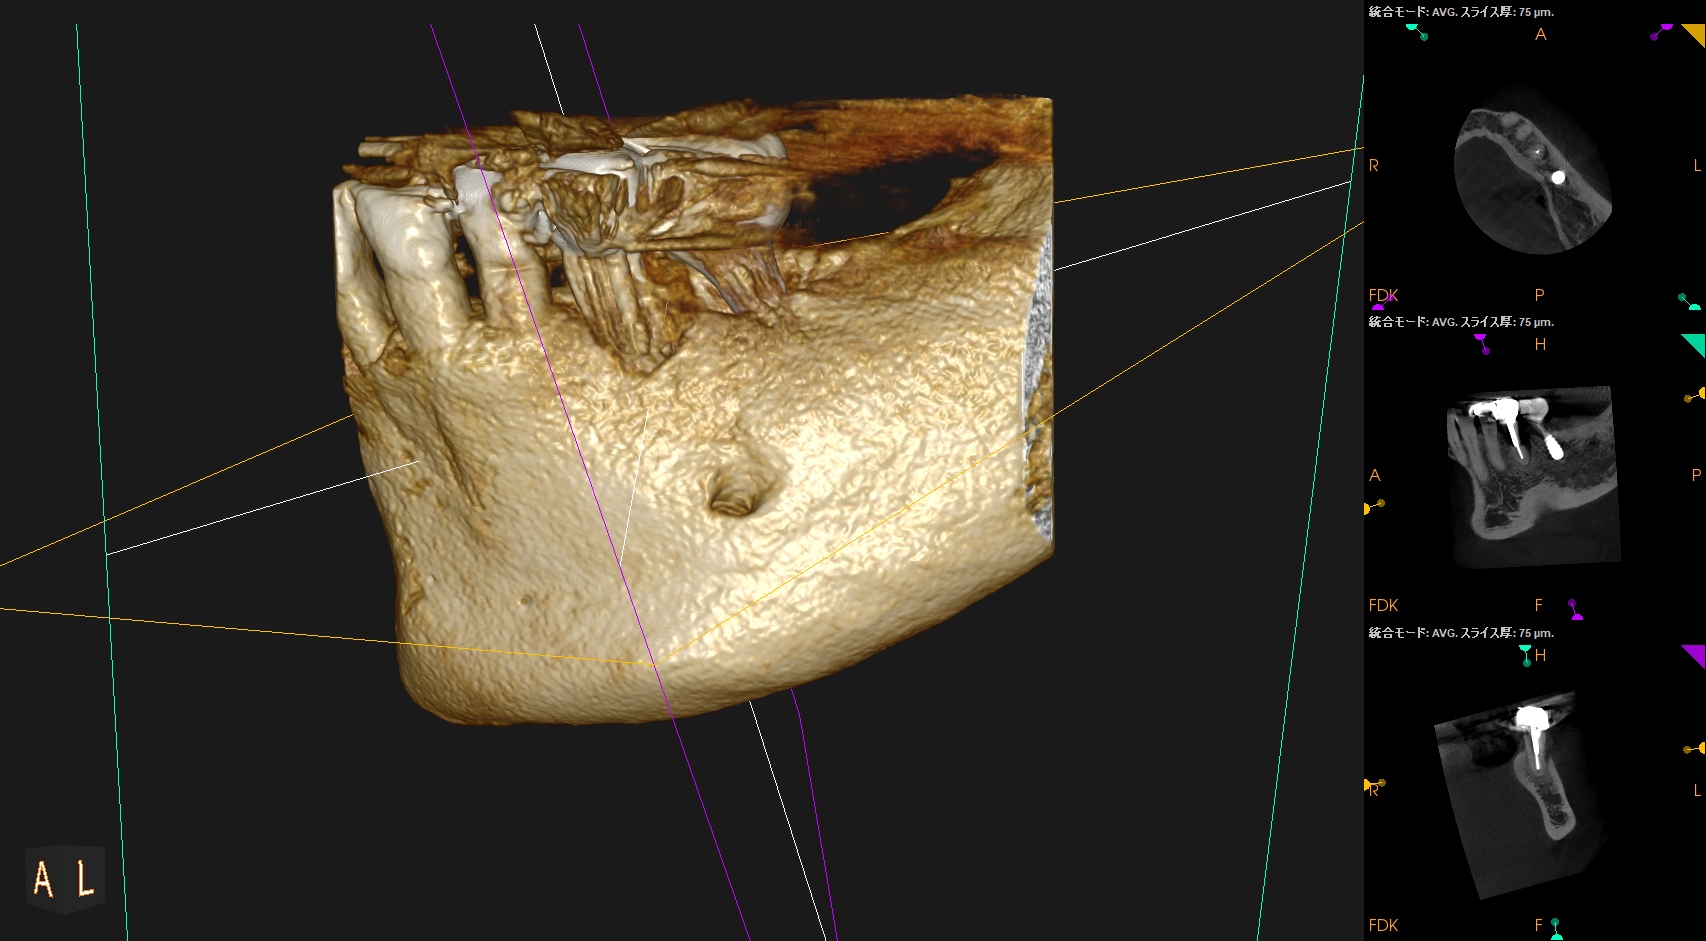

頬側の皮質骨は既にない。

VRFを想像させる絵だが、

術前の歯周ポケット測定では、#20は全周、Within Normal Limit(正常の範囲内)である。

術後にPA, CBCTを撮影した。